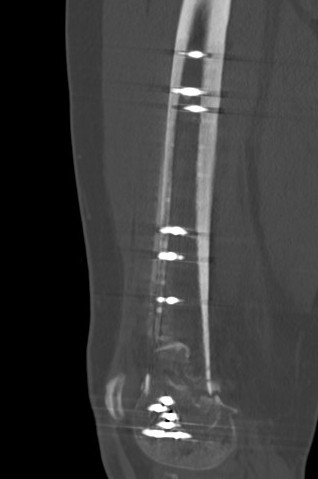

Plate + Nail

Nonunion

Incidence

Yoon et al. Arch Orthop Trauma Surg 2021

- meta-analysis

- 166/2156 nonunion (5%)

- no difference nail v plate

Risk Factors

- nonunion associated with obesity / open fracture / infection / stainless steel plates

Kiyono et al. J Orthop Surg Res 2019

- increased nonunion with medial fracture gap > 5 mm

- 96 patients

- more rigid plate screw constructs associated with nonunion

- avoid locking screws in the diaphysis

- 271 patients

- increased non union stainless steel plates compared with titanium plates